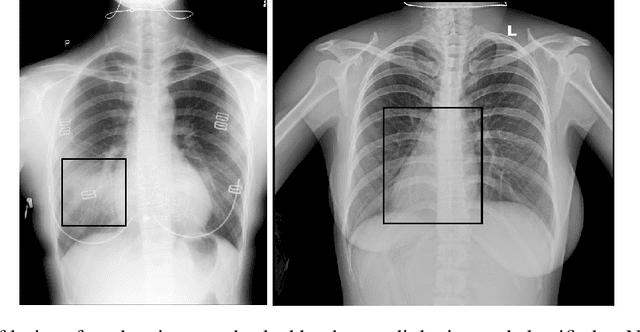

Abstract:The sudden outbreak and uncontrolled spread of COVID-19 disease is one of the most important global problems today. In a short period of time, it has led to the development of many deep neural network models for COVID-19 detection with modules for explainability. In this work, we carry out a systematic analysis of various aspects of proposed models. Our analysis revealed numerous mistakes made at different stages of data acquisition, model development, and explanation construction. In this work, we overview the approaches proposed in the surveyed ML articles and indicate typical errors emerging from the lack of deep understanding of the radiography domain. We present the perspective of both: experts in the field - radiologists, and deep learning engineers dealing with model explanations. The final result is a proposed a checklist with the minimum conditions to be met by a reliable COVID-19 diagnostic model.